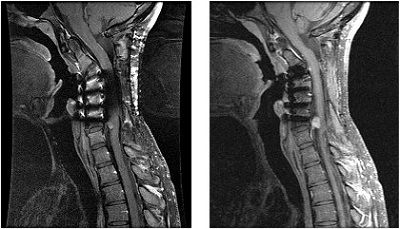

IDEAL uses a three-point Dixon method to acquire multiple echoes resulting in water only, fat only, fat and water in-phase, and fat and water out-of-phase processed images.

Although IDEAL can be used in any anatomical area, it is particularly useful in extremity and spine imaging. Indications for use include: C-spine, knee, foot and ankle, and brachial plexus.

In the presence of magnetic field inhomogeneities, the resonant frequency shift of fat and water typically varies over the image volume. In normal chemical suppression techniques such as fat SAT, areas of inhomogeneity result in poor fat suppression. IDEAL is designed to improve fat suppression in small FOVs and when the FOV is offcenter. This is accomplished by pre-shifting the computed fat image (correct to even sub-pixel dimensions using the Fourier transform shift theorem) before doing the addition and subtraction to synthesize the in- and out-of-phase images.

As a result, the dark line edges between water/fat boundaries that are associated with chemical shift (increased pixel shift) are eliminated. It also allows for low-bandwidth acquisitions to be used without the worry of chemical shift misregistration of fat, leading to reductions in NEX required for good quality, small FOV musculoskeletal scans.